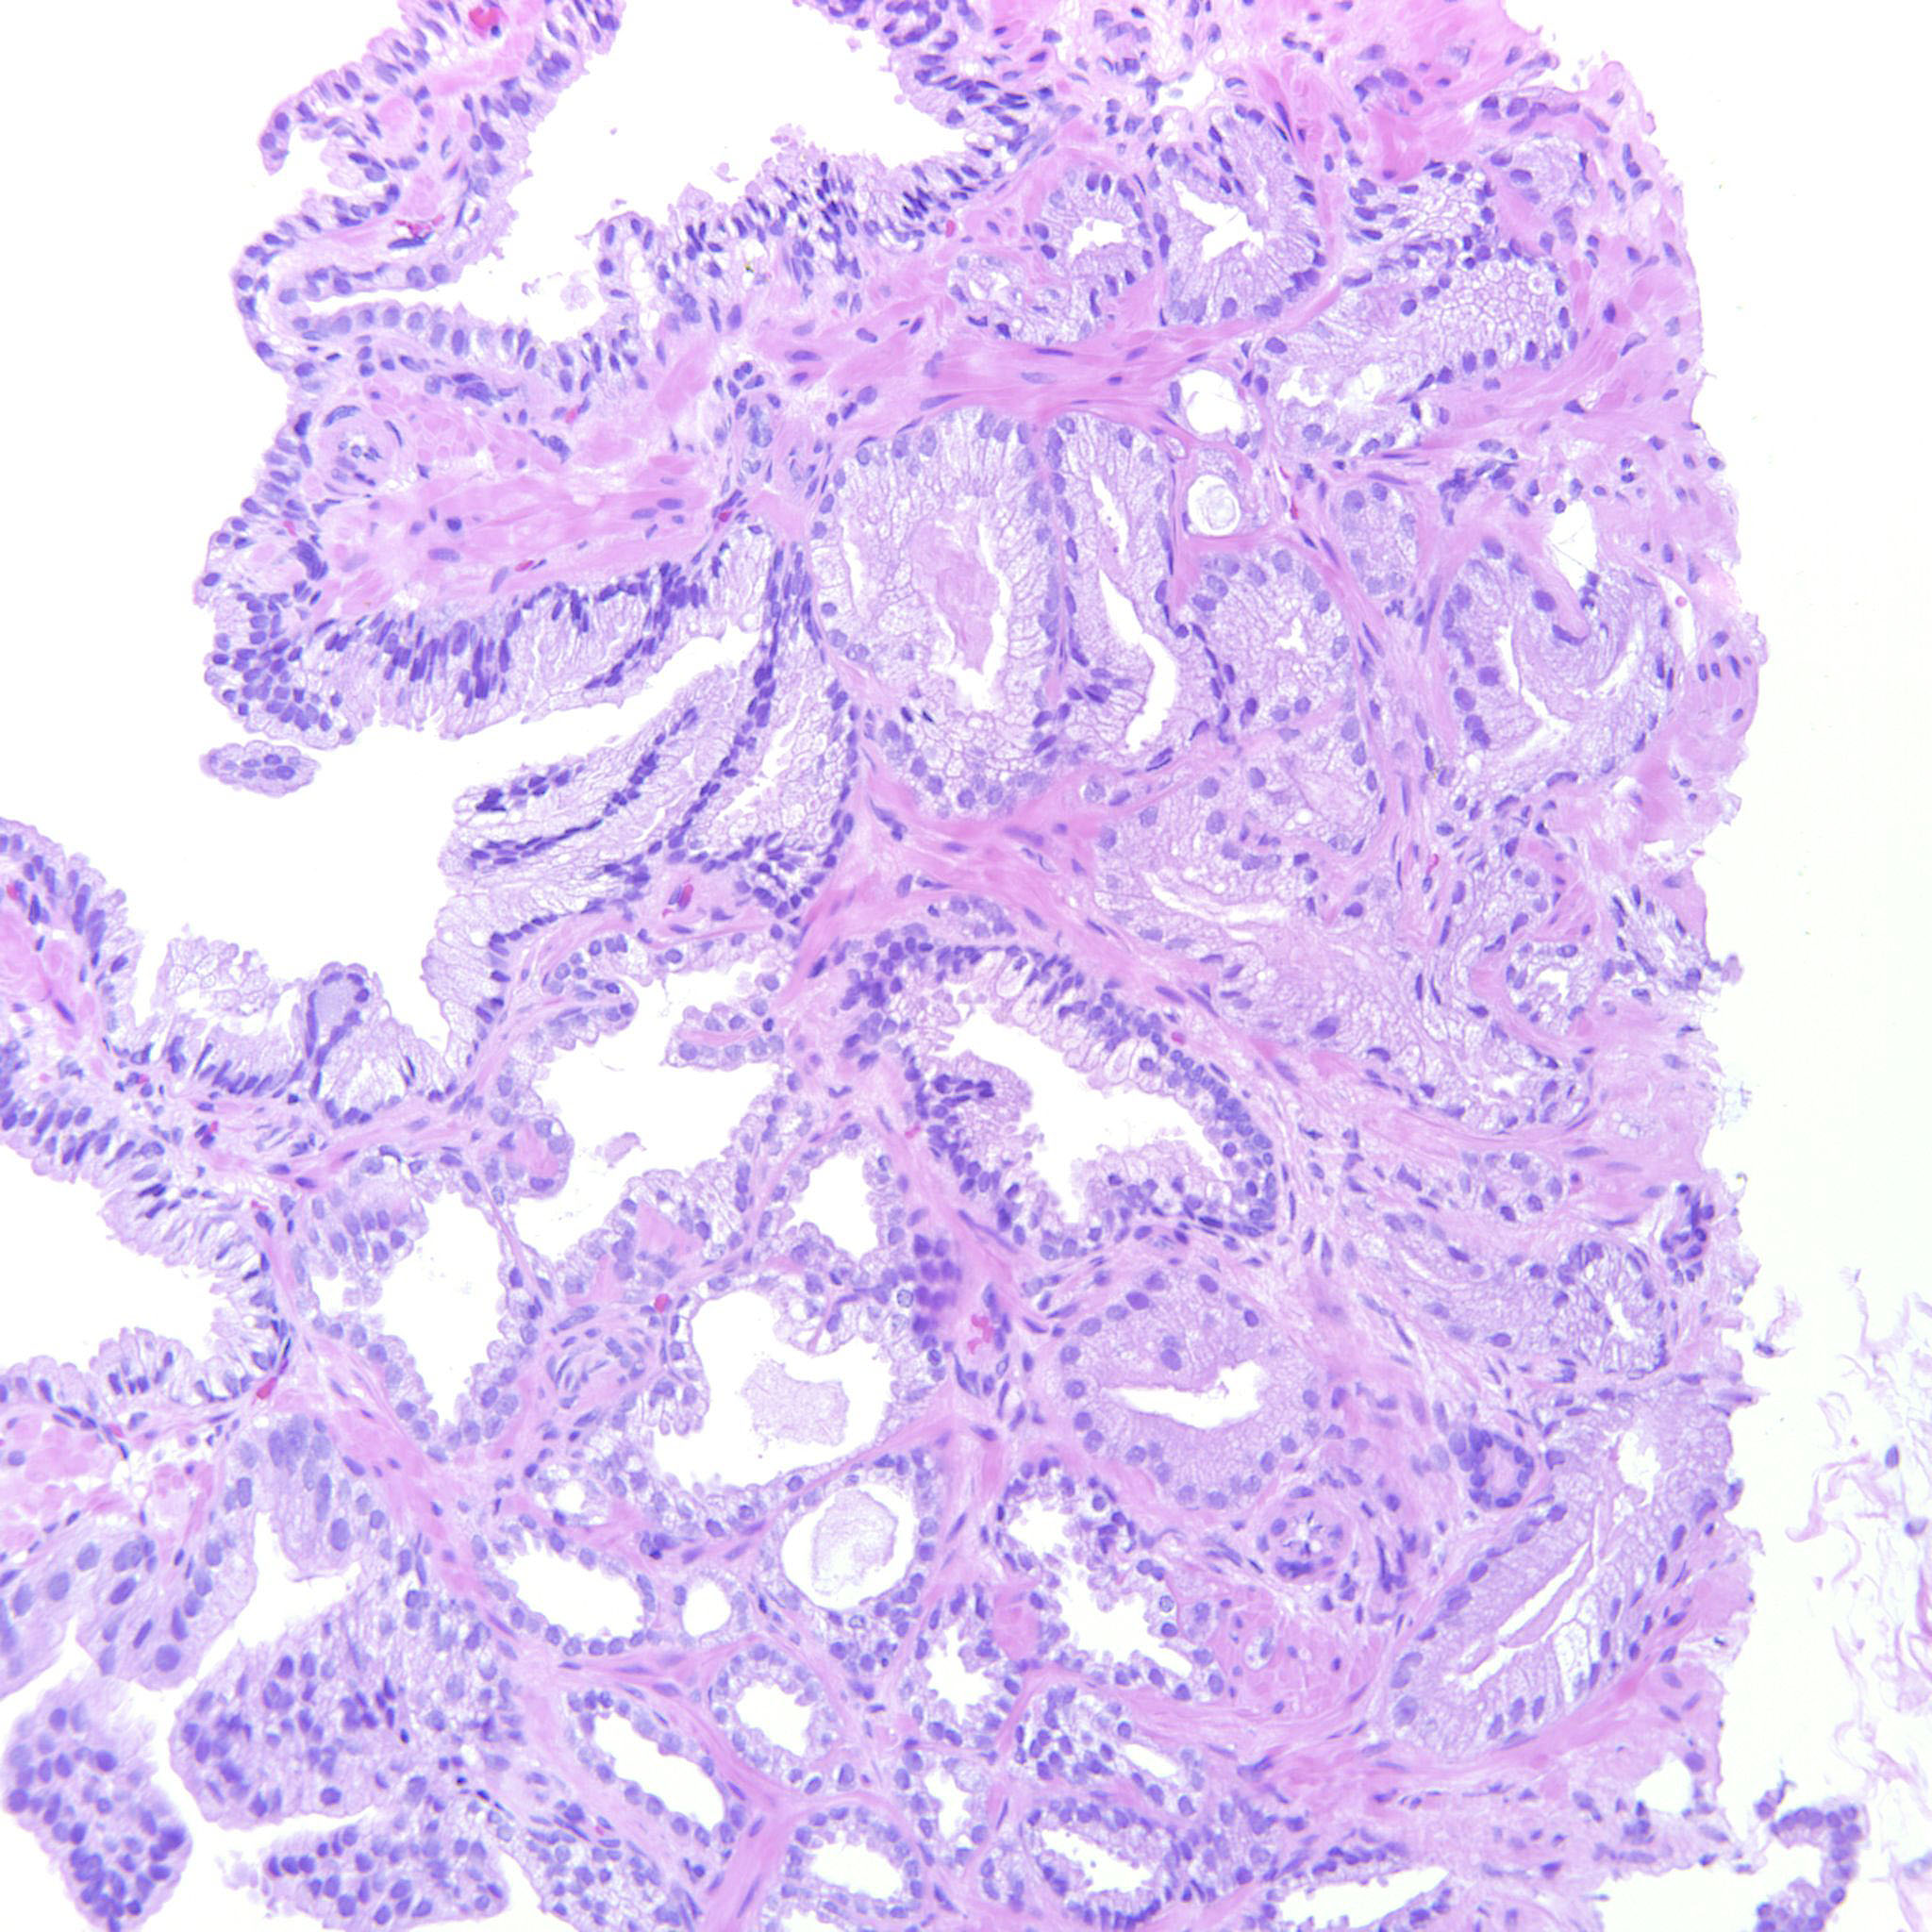

Prostate cancer grading

Case ID: 289